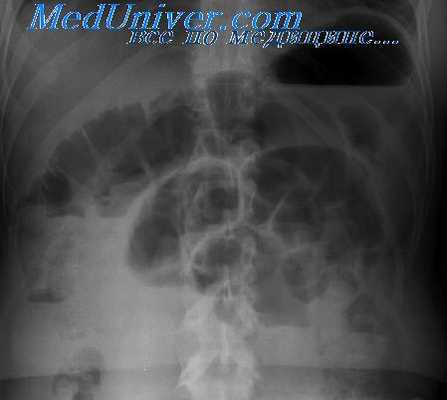

Рентгенография пассажа бария позволяет выявить препятствия на пути продвижения контрастного препарата, участки сужений и супрастенотического расширения кишки. Во время эндоскопического исследования врач производит биопсию для последующей морфологической верификации диагноза. В сложных для диагностики случаях проводят селективную ангиографию брюшной полости.

Во время рентгенологического исследования с применением зондовой энтерографии при экзофитном раке обычно обнаруживают небольших размеров, неправильной формы дефект наполнения с нечеткими и неровными очертаниями, а при циркулярной инфильтрации кишки — неравномерное сужение ее просвета на ограниченном участке, соответствующее пальпируемому уплотнению. Рельеф внутренней поверхности кишки в зоне поражения имеет атипичный вид, эластичность стенки нарушена. Супрастенотическое расширение кишки отсутствует или выражено весьма умеренно.

Рак слепой кишки встречается часто, растет, как правило, экзофитно, легко изъязвляется. Долго не нарушает проходимости кишки, имеющей широкий просвет и жидкое содержимое. Хорошо пальпируется. Клинически проявляется поздно, вызывая боли, похудание, анемию. Лишь при локализации опухоли в области подвздошно-слепокишечной заслонки возникают признаки частичной кишечной непроходимости. При рентгенологическом исследовании на одной из стенок кишки обычно выявляется крупный различной формы дефект наполнения с неровными, нечеткими контурами и бугристой поверхностью. Иногда опухоль циркулярно охватывает всю кишку. В центре опухоли нередко обнаруживается изъязвление. Стенка кишки в зоне поражения ригидна, складки слизистой оболочки на границе с опухолью разрушены.

Опухоли больших размеров могут выполнить весь просвет слепой кишки и обусловить симптом ее «ампутации»: подвздошная кишка, которая, как правило, в процесс при этом не вовлекается, непосредственно переходит в высокорасположенный «конец» толстой кишки. Истинная причина этой рентгенологической картины легко устанавливается при раздувании кишки газом, особенно при исследовании в латеропозиции на левом боку. Редко встречающиеся в слепой кишке эндофитные опухоли вызывают циркулярное сужение ее просвета и ригидность стенок, что отчетливо видно при исследовании в условиях двойного контрастирования.